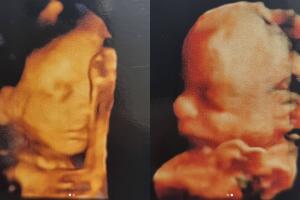

Claudia Álvarez compartió con sus fans un momento único al publicar por primera vez imágenes de sus mellizos desde el interior de su pancita de 6 meses de embarazada.

La protagonista de Vencer El Desamor compartió la noche de este lunes 22 de noviembre en su cuenta de Instagram dos imágenes con las ecografías que le realizaron y que dejan ver a su hijo e hija.

En una primera foto, aparece el bebé varón y en la siguiente la niña: "Gracias a Dios todo va perfecto con su desarrollo. Ya pesan medio kilo (1.1 libras) cada uno, pero mi espalda los siente como si pesaran mucho más", escribió la artista junto a las imágenes de las ecografías.

A la izquierda aparece el bebé varón de Claudia Álvarez y a la izquierda se muestra a la niña.